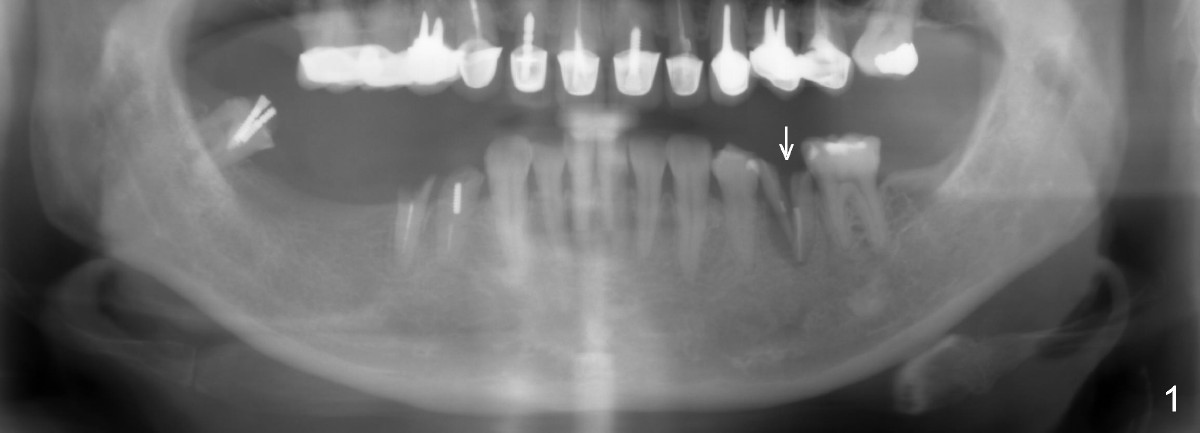

Six months postop, bone density around the implant increases (Fig.9).  There is slight gingival recession buccal to the implant (Fig.10 arrow).  A short abutment is placed and prepared short (Fig.11 A); the margin is prepared as low as possible in the implant (I).